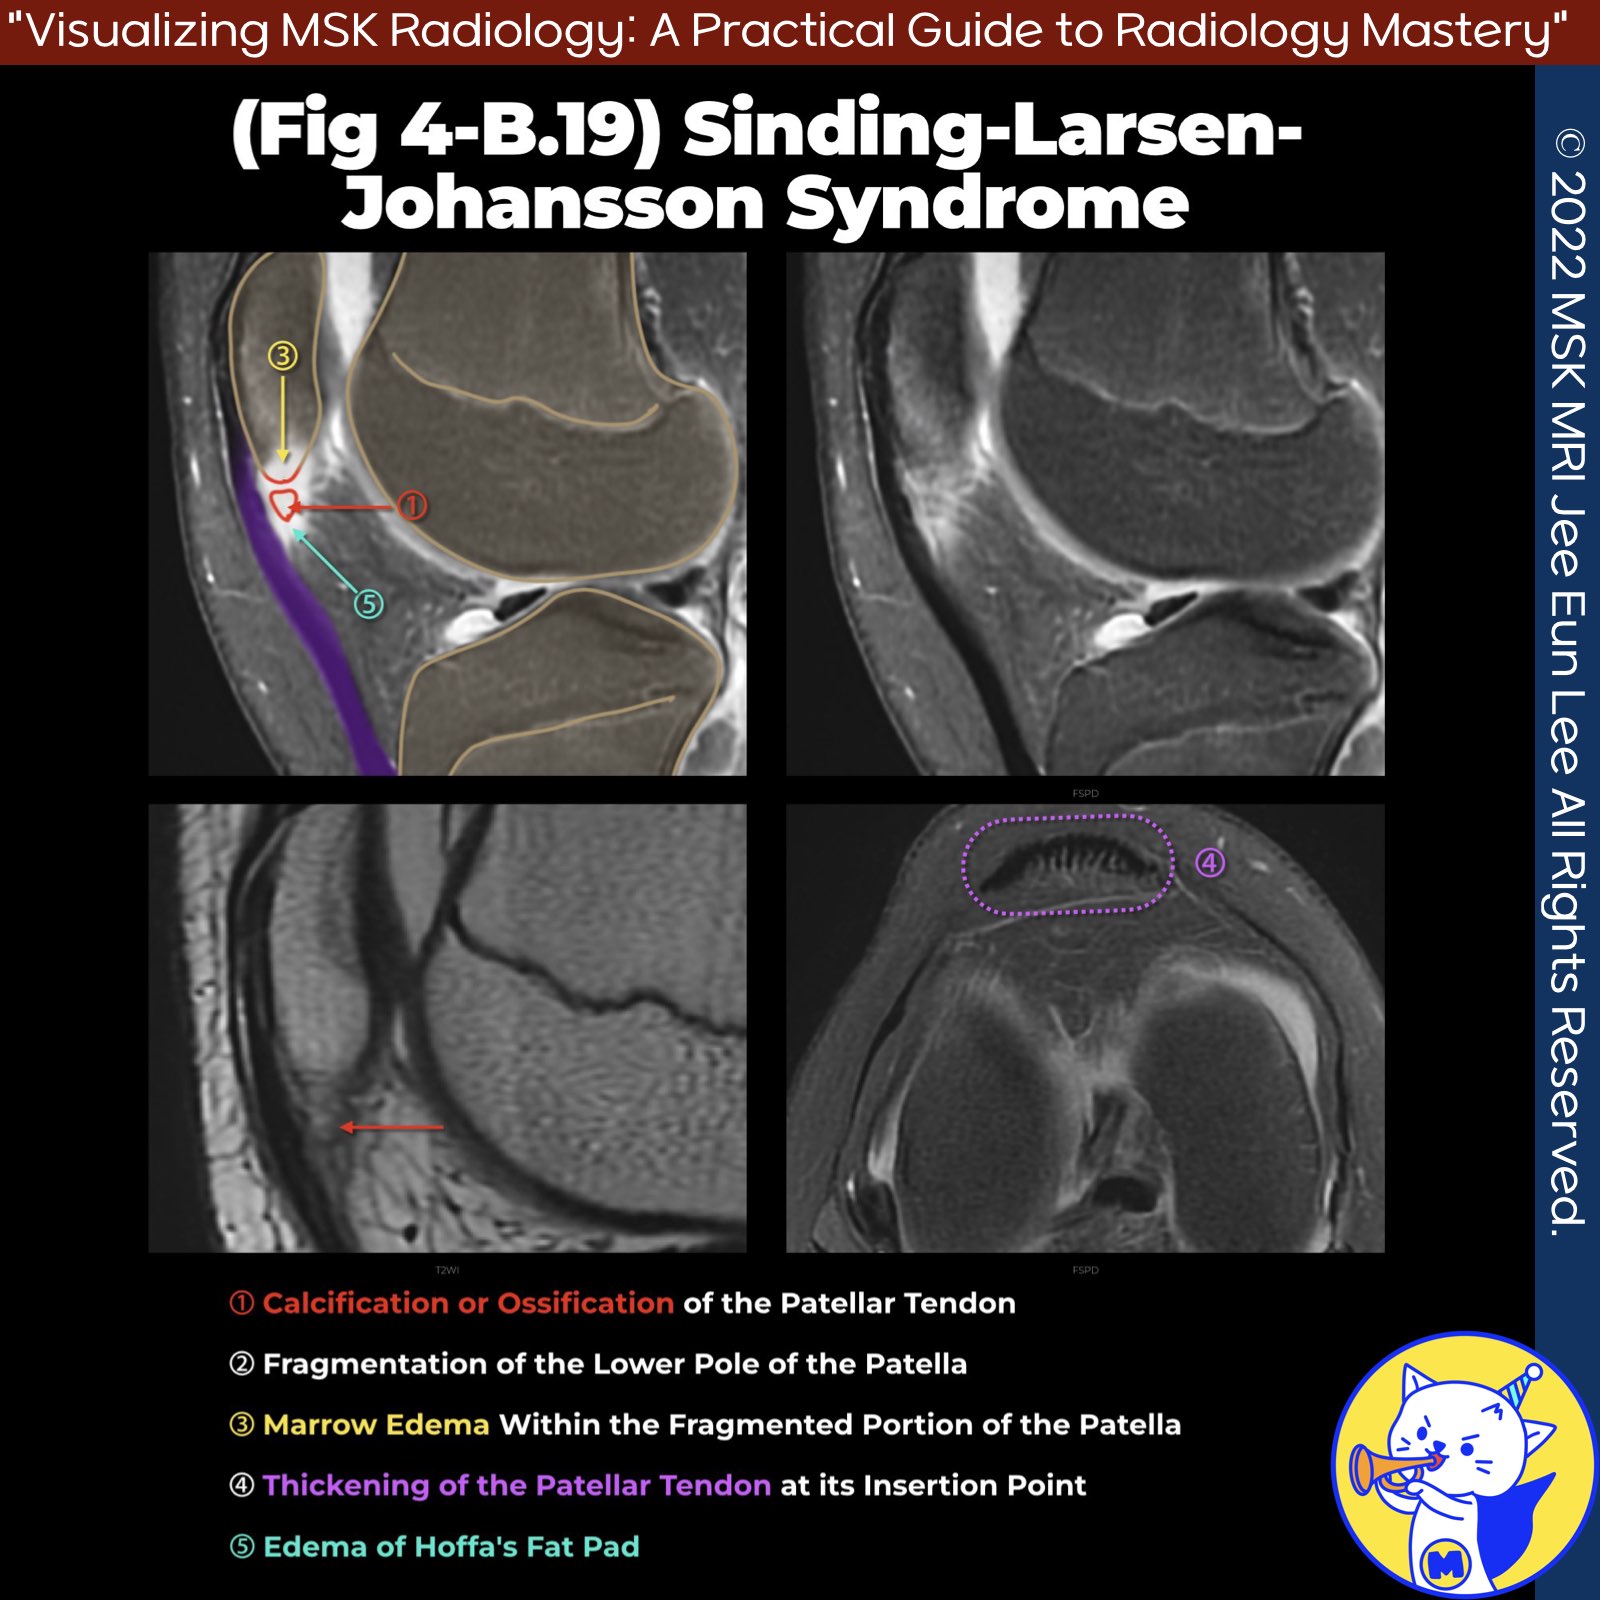

📌Sinding-Larsen-Johansson Syndrome

- Sinding-Larsen-Johansson syndrome, also known as jumper's knee, is caused by repetitive microtrauma to the patellar tendon at its attachment on the inferior pole of the patella.

- This syndrome is a type of traction apophysitis that occurs at the inferior pole of the patella.

- In contrast, Osgood-Schlatter disease is traction apophysitis at the tibial tubercle.

- Chronic traction can lead to heterotopic ossification, which is identifiable through imaging.

- MRI typically shows edema at the inferior pole of the patella and in the proximal portion of the patellar tendon and surrounding soft tissues.